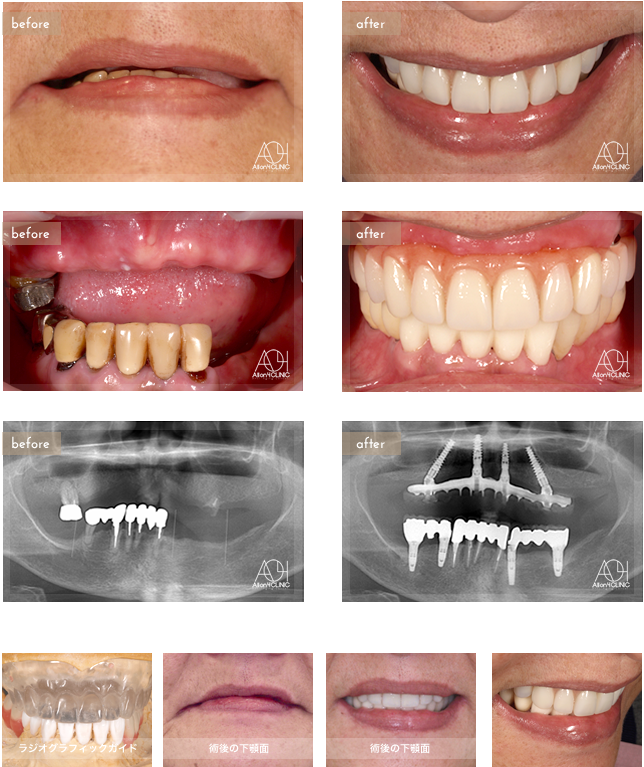

Sex : Female

- Maxilla All-on-4

上顎はNobel Active4本を埋入。上部構造はチタンPIBフレーム、人工歯タイプを採用。